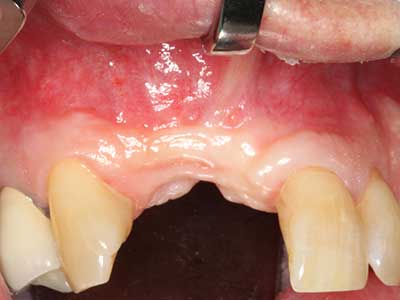

Zur Behandlung einer marginalen Parodontitis lassen sich eine initiale und chirurgische Therapiephase unterscheiden. Neben der Mundhygieneinstruktion und -motivation sollte in beiden Phasen eine suffiziente Reinigung der Wurzeloberfläche erfolgen, wobei im regenerativen Setting zumeist ein offener Zugang gewählt wird. Die Reinigung der Wurzeloberfläche kann durch die Verwendung spezieller Ansätze auch piezochirurgisch erfolgen, wobei unterschiedlich gebogene Instrumente auch schlecht zugängliche Bereiche wie Furkationen erreichen. Die systemimmanente Wasserkühlung spült dabei die gelösten Konkremente und Bakterien aus der Tasche. Um zusätzlich die Abtragung von Zahnhartsubstanz zu minimieren, wurde bei speziellen Systemen wie dem Piezomed ein Applikations-Feedback eingebaut. Hierbei wird die Abtragungsleistung konsequent reduziert, je mehr Druck auf den Parodontalansatz ausgeübt wird.